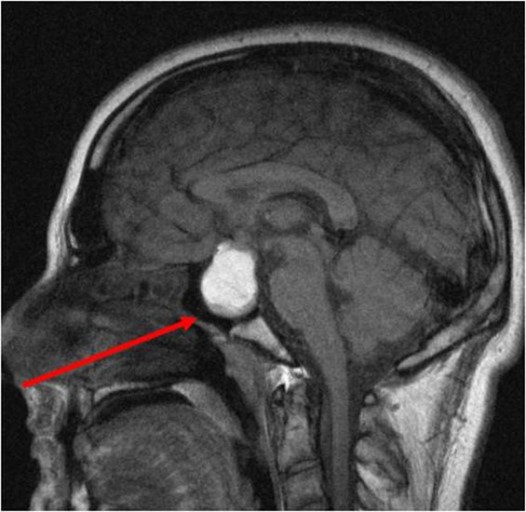

뇌하수체선종은 뇌하수체에 생기는 종양입니다. 뇌하수체는 뇌의 기저부에 위치한 작은 기관으로, 호르몬을 분비해 신체의 다양한 기능을 조절합니다. 뇌하수체선종은 양성 종양인 경우가 대부분이지만, 악성 종양일 수도 있습니다. 뇌하수체선종은 드문 질환으로, 전 세계적으로 연간 10만 명당 1~2명 꼴로 발생하고 남자보다 여자가 2배 더 많이 발생합니다.

CT, MRI 검사를 통해 진단할 수 있고, 뇌하수체선종이 의심되는 경우, 뇌하수체에서 분비되는 호르몬의 양을 측정합니다.